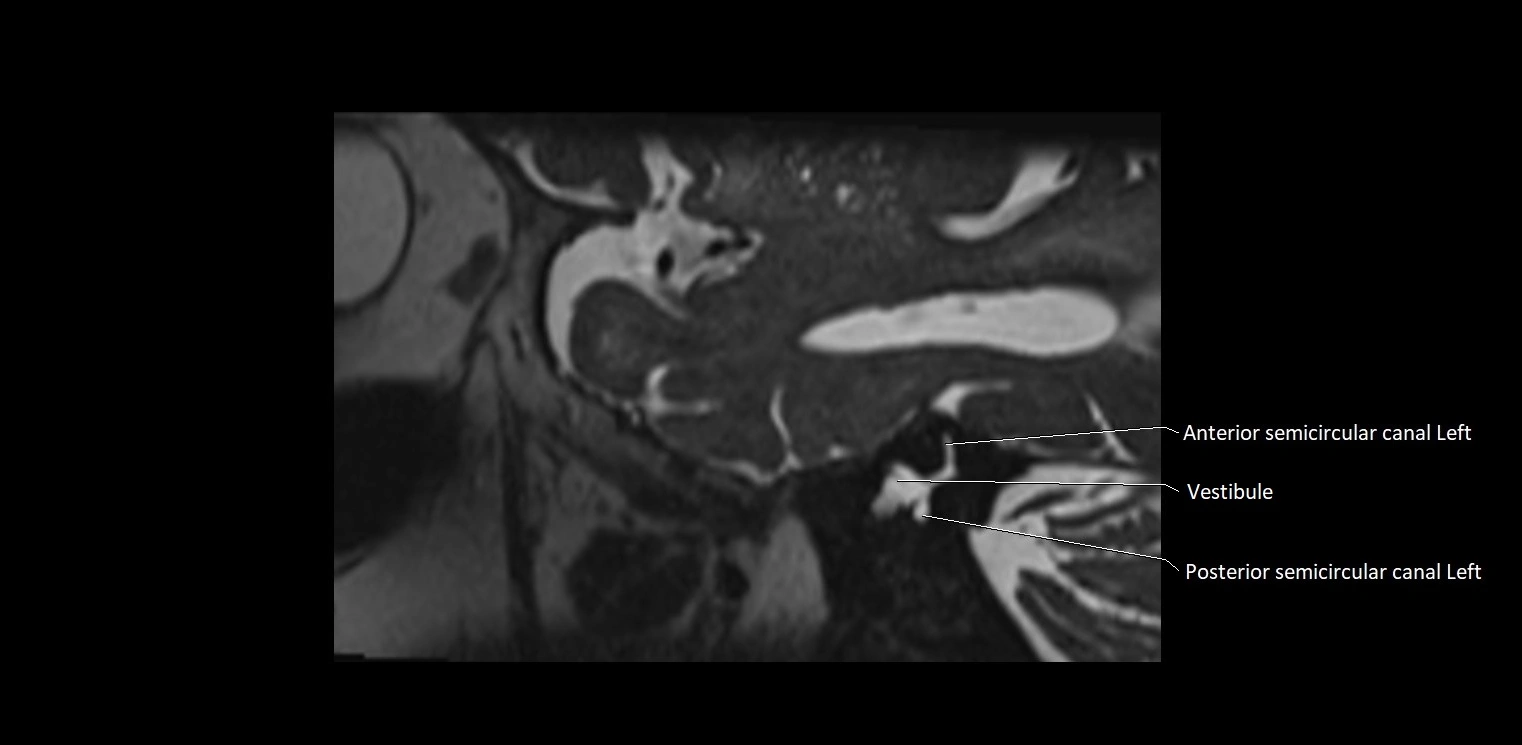

MRI Appearance

• The abducens nerve is a small, thin, linear structure

• Best visualized on high-resolution T2-weighted 3D MRI sequences (e.g., FIESTA or CISS)

• Seen as a hypointense (dark) line running from the brainstem at the pontomedullary junction, traversing the prepontine cistern, and entering Dorello’s canal under the petrosphenoidal ligament, then into the cavernous sinus, and finally the orbit

• May be challenging to visualize in standard MRI due to its small size

• Pathology may be inferred by absence, displacement, or enhancement of the nerve